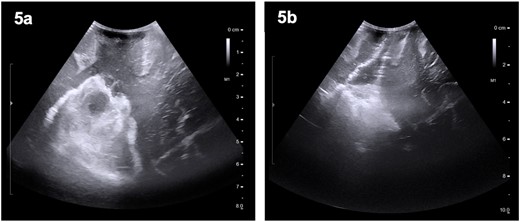

The patient was started on oral dexamethasone, resulting in the improvement of his headaches. The differential diagnosis based on imaging findings included an atypical meningioma, central neurocytoma, choroid plexus papilloma or carcinoma, ependymoma or an oligodendroglioma. He underwent a right parietal craniotomy with gross total resection of the lesion. Intraoperatively, use of the Vycor™ ViewSite Brain Access System (VBAS) was utilized, which allowed for optimized surgical site access, and reduced the risk of brain retractor injury to surrounding structures, namely the precentral gyrus. This was combined with intraoperative ultrasound (Fig. 3), which provided real time imaging and guided the extent of the resection. In addition, neuromonitoring and neuronavigation (Fig. 2) were incorporated to further reduce the risk of damage to surrounding structures. As part of the neuromonitoring, motor evoked potentials (MEPs) were performed to identify the precentral gyrus prior to insertion of the VBAS (Fig. 4), ensuring that any resection occurred posterior to the motor strip. During surgery, it was noted that the lesion was haemorrhagic and easily friable, with evidence of a previous recent haemorrhage.

Preoperative (5a) ultrasound images depicting a heterogenous mass with hyperechoic and hypoechoic regions. Post-operatively (5b), a hyperechoic region is noted; however, no distinct lesion is identified.

Post-operative course

The patient remained neurologically intact post-operatively and was discharged 5 days after surgery. A post-operative MRI revealed some intraventricular enhancement but no clear residual tumour (Fig. 5), likely indicating a complete resection of the lesion. He was seen in clinic 4 days and again 3 months after discharge and was noted to be recovering well.